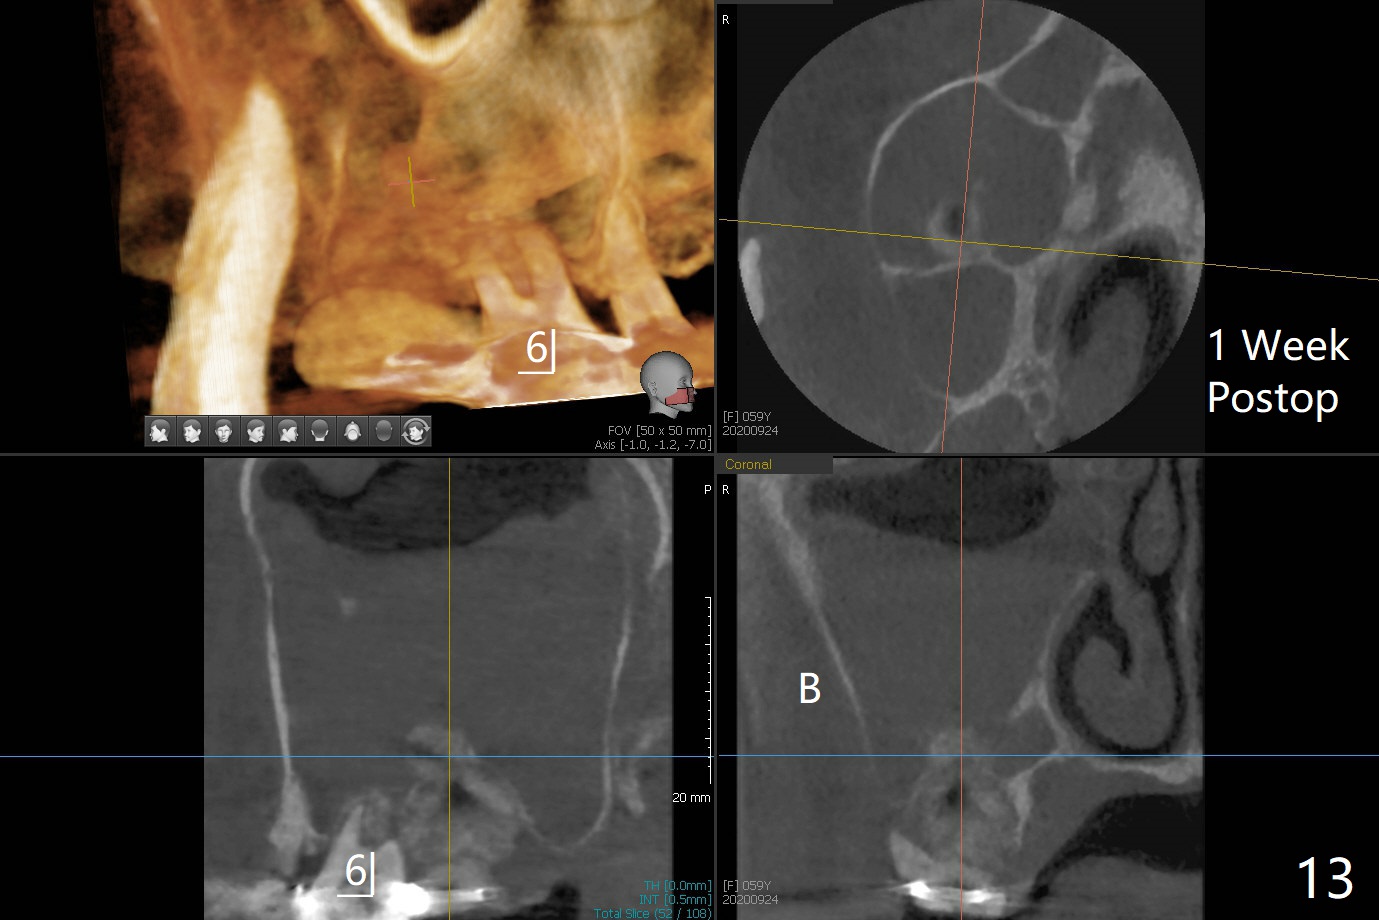

第二磨牙位点保留后,牙周敷料容易脱落,尤其上颌,本文介绍一种方法增加固位。右上七严重牙髓牙周综合征,拔出后使用刮匙除去骨面肉芽组织,颊侧骨板缺失,附着在颊侧粘骨膜上的肉芽组织使用一种叫Stieglitz angled, diamond splinter forceps (德国产,图一,二)撕下来。彻底清除炎性组织必须多次刮治,之间塞入带有灭滴灵(图三:粉剂)和1比50,000肾上腺素局麻药纱布(图四)止血,取出纱布,牙槽窝视野好,继续去除残余的肉芽组织。牙槽窝底部穿孔,用无齿刮匙稍微扩大穿孔后,使用图五下面小的骨粉输送器,将少量骨粉(粘性)送到穿孔处,推入上颌窦(图七:S),之后使用大的骨粉输送器(图五上面),把大量骨粉送到牙槽窝,使用图六上面大的,长的充填器,压实骨粉(图七),骨粉表面放置PRF膜和不可吸收膜(图八),在第一磨牙时安置粘固一个间隙维持器(图九,十),最后铺上牙周敷料(图十一),检查咬合空间,没有干扰。There are sign and symptom of sinusitis 1 week postop; large amount of bone graft retains in the socket by the periodontal dressing and spacer (Fig.12). The sinus membrane (Fig.7 immediate postop) thickens 1 week postop (Fig.13). Augmentin and Medrol Dose Pak are prescribed. 上颌窦炎一周后消失,腭侧牙周敷料丢失,伤口好像正常愈合(图十四)。术后三周牙周敷料由于大量水枪冲洗脱落(图十五)。因为病人需要离城两个月,间隙保持器撤除(图十六),不可吸收膜腭侧稍微外翻 (<),可能有利于术后五周自行脱落。No Deviation SP 下一个病例 位点保留后Xin 导板与张口度 第一磨牙即种 Wei, DDS, PhD, MS 1st edition 09/17/2020, last revision 04/30/2021